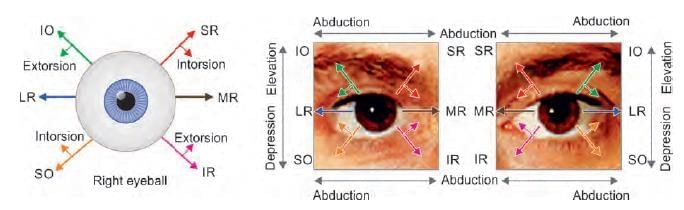

A patient presented with squint in right eye, as shown below. Identify the nerve lesioned in this case: (NEET-PG 2020p)

A child presented with left sided head tilt. On head straightening, there is right hypotropia, which increases on tilting head to right side. Which of the following muscle is paralysed? (AIIMS June 2020)

Match the following cranial nerves with their corresponding actions: (INI-CET May 2023)